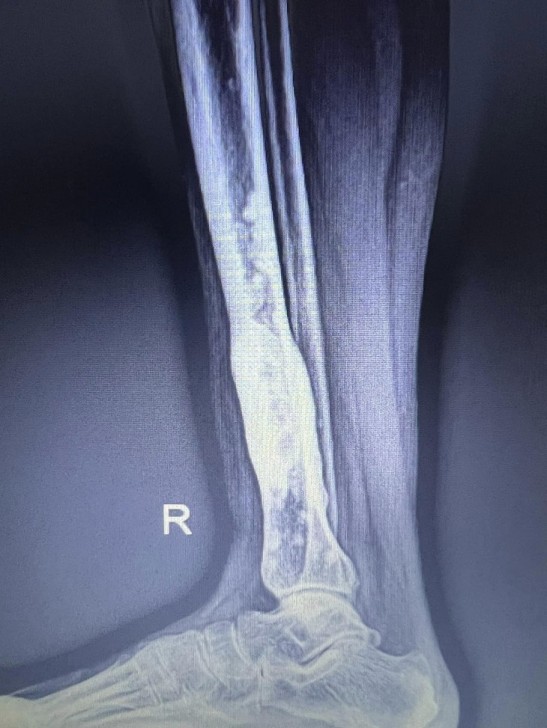

AFN.az xəbər verir ki, tanınmış həkim Aydın Əliyev bu sahədə vəziyyətin getdikcə ağırlaşdığını bildirib. O, xəstələrdən birinin müayinə nəticələrini paylaşaraq bunları yazıb: “Onkoloji xəstəliklərin müayinə və müalicəsinin hələ də icbari tibbi sığorta tərəfindən qarşılanmamasının daha bir qurbanı. Sağ qamış sümüyündəki törəmənin maddi imkansızlıq səbəbindən vaxtında və sistemli müalicə və ya əməliyyat edilməməsi səbəbindən fəqərələrə, qabırğalara, kürək, çanaq sümüklərinə, ağciyərə çoxsaylı metastazları. Demək olar ki, adam həyatını itirib”.